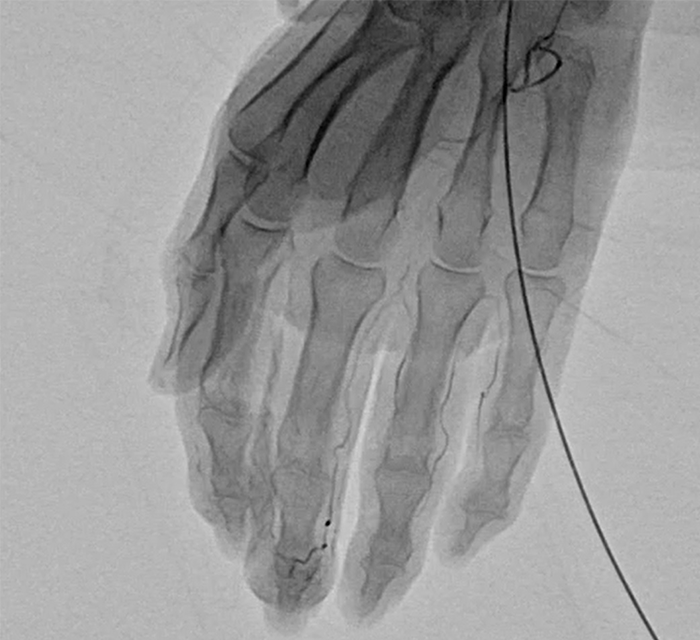

ヘパーデン結節や母指CM関節症などの痛みの原因になっているモヤモヤした異常な血管を撃退する治療法です。 病気の原因になっているモヤモヤした血管ができることで痛みを発生させてしまうことが判明し、 ピンポイントで治療できるように極めて細いチューブ(カテーテル)でモヤモヤした血管に薬剤を注入して治療を行います。

治療する部位にあわせて、手首または足首に局所麻酔を行い、極めて細いチューブ(カテーテル)を使って、血管に挿入します。エコーで血管内にあることを確認後に薬剤を注入し、5分から10分ほどで終了します。

提供元:Okuno Clinic. 奥野祐次医師